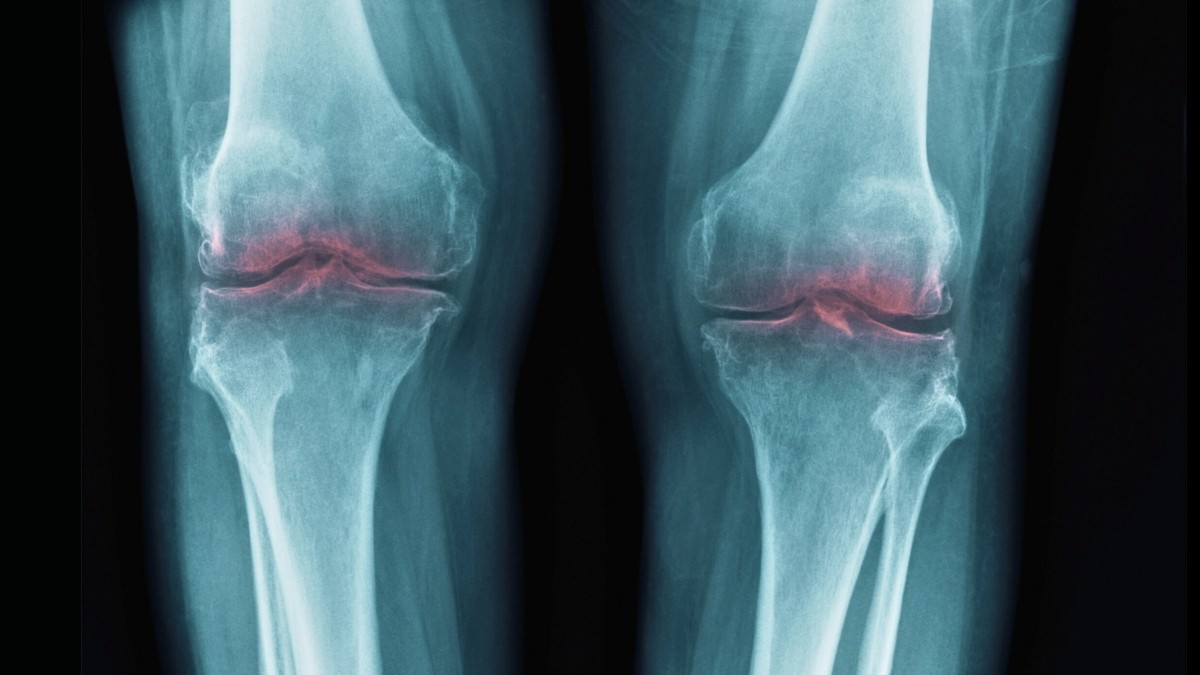

Un nuevo estudio de la Universidad de Stanford ha identificado una proteína clave, la 15-PGDH, como una de las principales causas de la pérdida de cartílago en las articulaciones que envejecen. Los hallazgos sugieren que el bloqueo de esta proteína podría regenerar el cartílago dañado, ofreciendo un tratamiento potencial para la osteoartritis que evita la necesidad de una cirugía de reemplazo de articulaciones.

Los investigadores saben desde hace mucho tiempo que el 15-PGDH aumenta con la edad e interfiere con los mecanismos naturales de reparación de los tejidos del cuerpo. Este estudio demuestra que esta proteína está directamente relacionada con la degradación del cartílago en la osteoartritis: la inflamación y el dolor causados por el colágeno dañado en las articulaciones.

En pruebas con ratones mayores, la introducción de un inhibidor de 15-PGDH provocó un engrosamiento significativo del cartílago en rodillas previamente desgastadas. Se observaron resultados similares en ratones jóvenes lesionados, en los que el inhibidor protegía contra el desarrollo de osteoartritis. En particular, los ratones con lesiones simuladas del LCA no desarrollaron artritis cuando fueron tratados con el inhibidor.